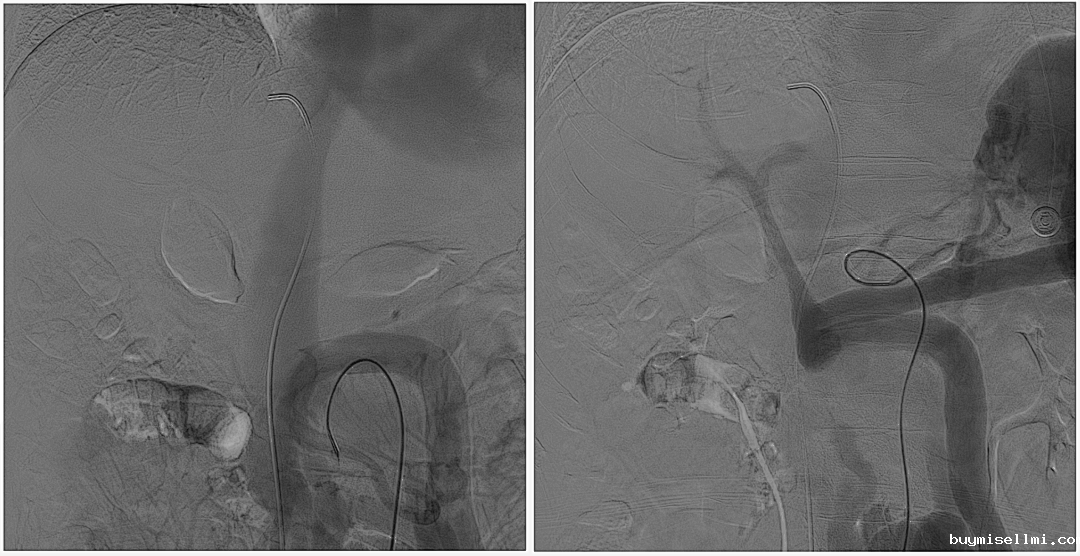

至肠系膜上动脉行间接门静脉造影,未见门静脉显影,可见巨大异常分流道,遂至脾动脉行间接门脉造影可见门静脉异常纤细,肠系膜下静脉见异常分流道形成

以微导管行肝动脉标记辅助穿刺,门静脉造影显示血流呈离肝状态

超选至肠系膜下静脉异常分流道,予以栓塞18mm的Amplatzer vascular plug及适量25%生物胶,造影示异常分流道消失

8mm覆膜支架释放于肝内穿刺道,考虑门脉纤细,遂以6mm球囊后扩张

异常分流道栓塞后,再次行门静脉造影,血流呈向肝状态,食管胃底曲张静脉较前更显著,微导管超选至曲张的胃冠状静脉,予以弹簧圈及25%生物胶栓塞,造影示曲张静脉消失,肝内门脉显影较术前显著改善